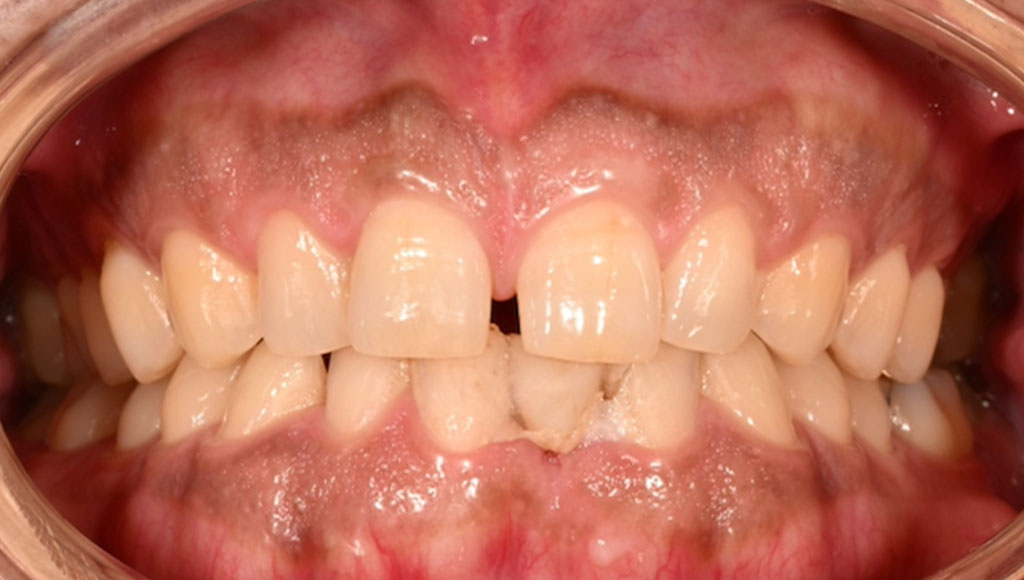

Before1

患者様の主訴

40代女性。横浜市在住。左上1番右上1番のクラウンに着色があり審美的に問題を抱えていたため、ご来院されました。

診断結果

ジルコニアクラウンを装着するために元のブリッジを外し、歯の形成を行いジルコニアクラウンをセット

治療内容

ジルコニアクラウンを装着するために元のクラウンを外し、歯の形成を行い光学印象(プライムスキャンによる)型取りを行いました。光学印象のデータを元に当院の院内技工室にてデジタル加工を行い、ジルコニアクラウンを作成し、セットを行いました。

治療期間

2回

治療費用

総額:330,000円(税込)

◼️内訳

ジルコニアクラウン(前歯):150,000円(税込)/1本×2本

光学印象(プライムスキャン)

リスク・副作用

補綴物の脱落・欠落、咬合違和感、色調補正